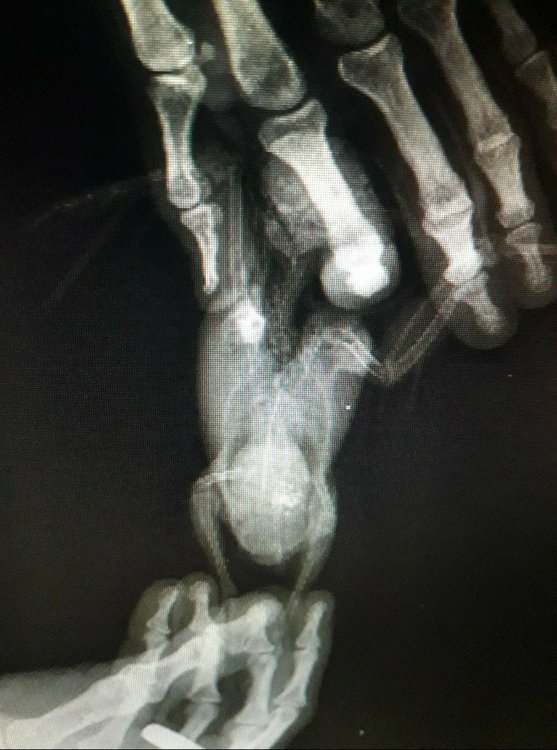

Малыш 87 Опубликовано 12 декабря, 2019 Автор #23 Опубликовано 12 декабря, 2019 Делали ренген Сказали вроде как немного увеличена

Малыш 87 Опубликовано 13 декабря, 2019 Автор #28 Опубликовано 13 декабря, 2019 Мне отдали только диск с ренгеном

Кузяныч Опубликовано 13 декабря, 2019 #31 Опубликовано 13 декабря, 2019 @Малыш 87, а результаты анализа помёта на листе бумаги вам выдавали на руки? Все эти расспросы я затеял потому что при увеличении печени (гепатомегалии) больше подходит гепатовет. Гептрал, как по мне, назначают при явных тяжёлых поражениях, одним из симптомов которых является помёт жёлтого / оранжевого цвета. И ещё я хотел бы увидеть результат анализа помёта чтобы сопоставить их с внешним видом помёта на предоставленном вами снимке.